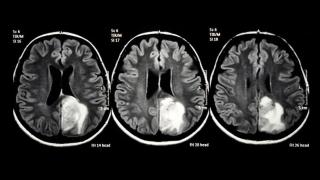

Expertos médicos alertan sobre la inequidad en el acceso a TTFields en el tratamiento del glioblastoma en España

La terapia con campos eléctricos está disponible en más de 15 hospitales públicos en España, pero no en Euskadi, Andalucía o Comunidad Valenciana.

En el marco del 'workshop' organizado por ASTUCE Spain bajo el título 'Más allá del diagnóstico: lo que no sabemos (ni hablamos) del cáncer cerebral', médicos de referencia en neurooncología advirtieron sobre la desigualdad que existe en España en el acceso a terapias innovadoras como los campos eléctricos TTFields, una tecnología con eficacia demostrada en el tratamiento del glioblastoma.

“Estamos hablando del único avance en 20 años que mejora la supervivencia en glioblastoma, y no está disponible en todo el país”, denunció la doctora María Ángeles Vaz, presidenta del Grupo Español de Investigación en Neurooncología (GEINO).